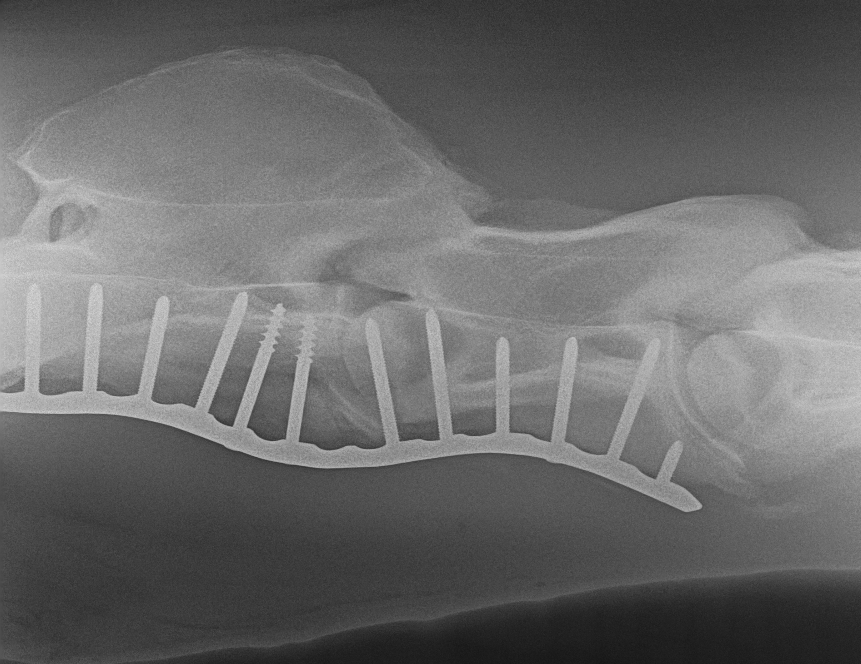

Cervical Fracture - CT and Surgical Repair

X-ray image of a dog's skull showing a metal grid and an internal screw fixation.